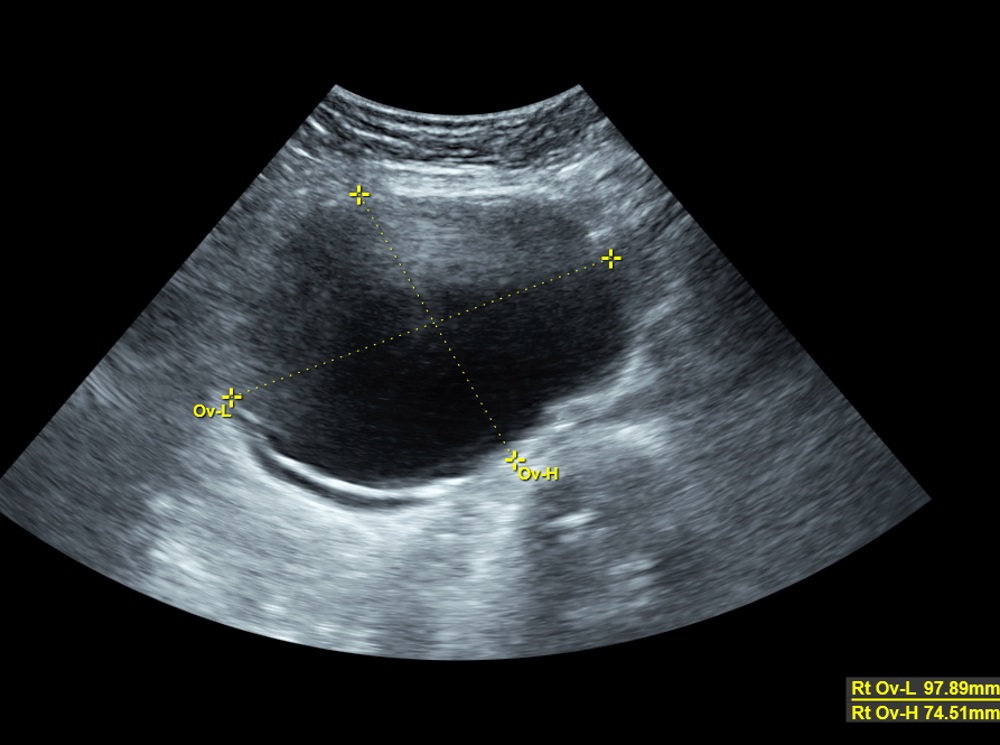

Kisti olup hamile kalanlar. çikolata kisti olup sol tüpü kapalı hamile kalanlar çikolata kisti. Bunun opere olması şart değil. şubatta kontrolüm var dua ediyorum o zamana kadar hamile kalayım diye teşekkür ederim geçmiş olsun size de dermoid kistler ilaçla küçülmüyor maalesef benim de ilk dr görmemişti kisti alttan ultrasonla bakmasına rağmen 2.

Kizlar ankarada 2 devlet kadindogum hastanesi gezdim ama beni mahvettiler. çikolata kisti olup sol tüpü kapalı hamile kalanlar çikolata kisti. Merhaba kistler türüne göre gebe kalmada sıkıntı yaratır çikolata kisti de hamile kalmaya engel olan kistler den biri. Kistimin polikist oldugunu adet gorunce gectigini soylediler ve suan 2 yillik evliyim ozel hastane adini cok duydugum hulisi bulent zeynelogluna gittim dermoid kistimin oldugunu soyledi ameliyat oldum bugun 3.